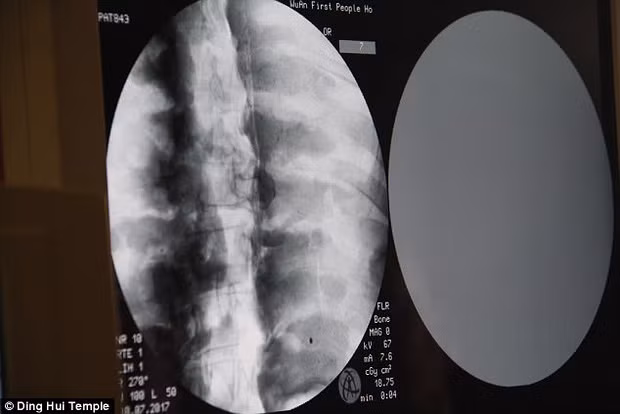

Cụ thể, các chuyên gia tiến hành chụp X-quang xác ướp nhà sư Từ Hiền. Nhờ vậy, họ phát hiện thi hài nhà sư Từ Hiền vẫn còn đầy đủ xương cũng như sọ não.

Theo các chuyên gia, xương hàm trên, hàm dưới, xương sườn, cột sống và tất cả khớp của nhà sư Từ Hiền đều hoàn chỉnh. Điều này khiến giới khoa học cảm thấy bất ngờ và khó tin.